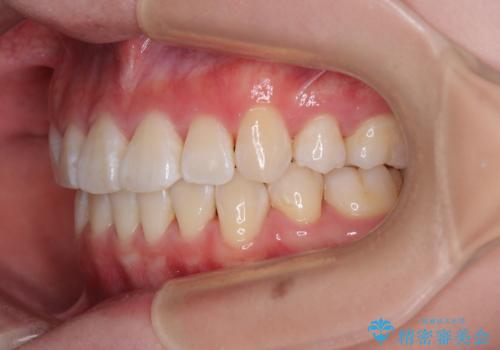

- 前歯がくちばしのように飛び出していることを気にして来院された患者様です。

唇が前方に突出している横顔が気になっているため、上下左右の第一小臼歯4本を抜歯し、ワイヤー装置にて矯正治療を行うこととしました。

わずか2年弱で一気に口元が変化し、患者様には大変満足していただけました。